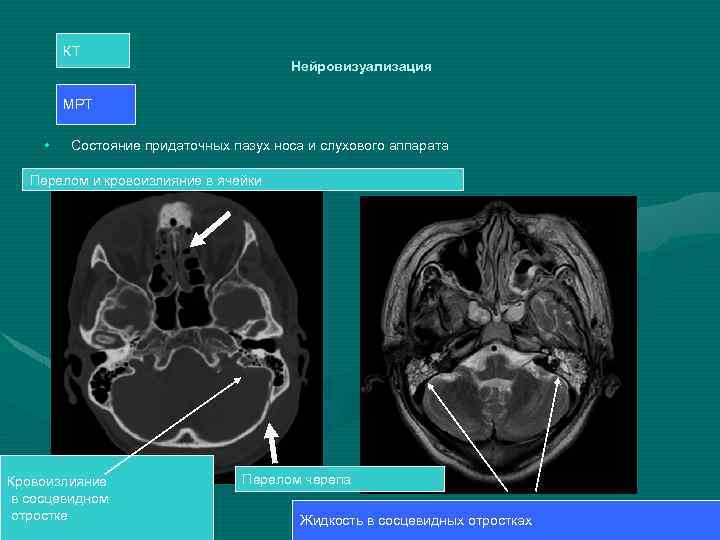

КТ Нейровизуализация МРТ • Состояние придаточных пазух носа и слухового аппарата Перелом и кровоизлияние в ячейки Кровоизлияние в сосцевидном отростке Перелом черепа Жидкость в сосцевидных отростках